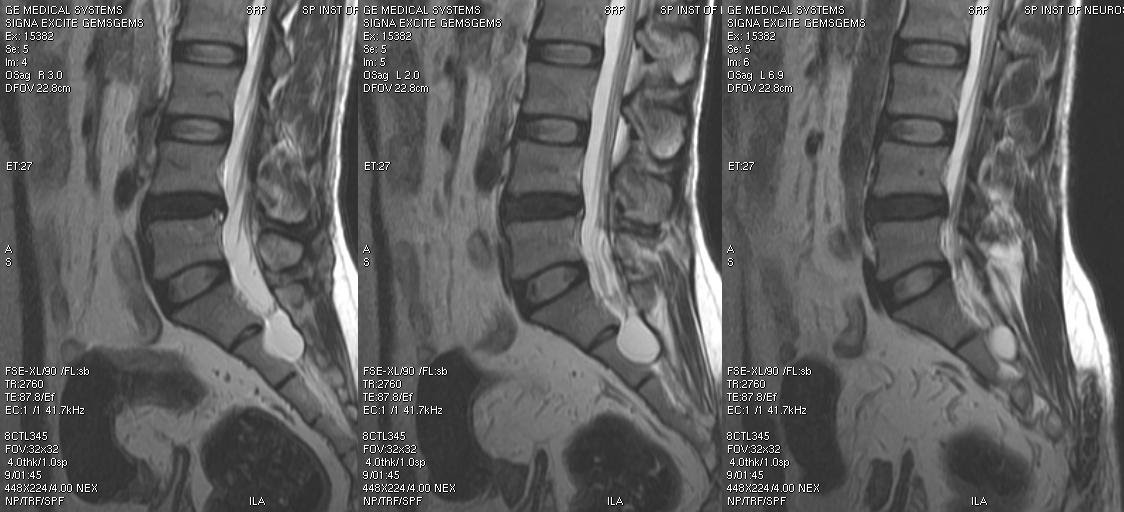

Dr Balaji Anvekar FRCR Tarlov cyst MRI

Le Cisti di Tarlov comunemente si presentano nella regione sacrale, in prossimità del ganglio della radice dorsale tra gli strati del cosiddetto perinevrio e dell'endonevrio. Tali formazioni sono state in primo luogo descritte nel 1938 dal Dr. I. M. Tarlov (Tarlov IM: Perineurial cysts of the spinal nerve roots.. A volte sono asintomatiche, ma possono crescere e causare sintomi come dolore nell'area dei nervi colpiti, intorpidimento, incontinenza, impotenza e debolezza. Le cisti di Tarlov colpiscono più le donne che gli uomini, anche se l'effettiva incidenza della malattia non è nota: si stima che ne sia colpito tra il 4,6 e il 9% dell'intera.